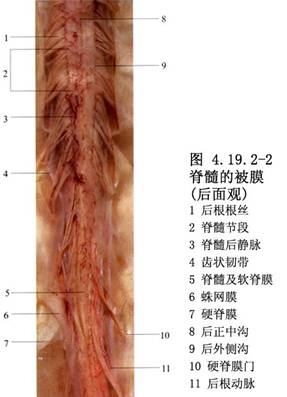

硬脊膜血管畸形亦稱硬脊膜動靜脈畸形(spinal dural AVMs),目前,多稱爲硬脊膜動靜脈瘻(spinal dural arteriovenous fistulae)。由於選擇性脊髓血管造影的開展和顯微手術的應用,對本病的發現率已明顯增加。畸形血管中含有供血動脈和引流靜脈,以及動靜脈之間的異常分流,亦可有畸形血管團。脊髓功能障礙症狀的產生,主要是脊髓的迴流靜脈內有動脈血的注入,使迴流靜脈內的壓力不斷升高所致。Symon(1984)報告的78例椎管內AVM中有55例位於硬脊膜或與硬脊膜表面有連屬。Rosenblum(1987)報告的81例中,硬脊膜AVM佔33%。其與硬脊膜內或脊髓AVM的不同點是:①本病好發於高齡病人,平均年齡爲59歲;②是後天性疾病;③多以疼痛和進行性癱瘓爲首發症狀,極少發生出血;④供血動脈均來自肋間動脈或腰動脈的硬脊膜分支;⑤病竈多位於椎間孔區,畸形血管團或動靜脈瘻埋置在覆蓋神經根及其附近的硬脊膜中,可有增粗且動脈化的引流靜脈穿過硬脊膜,紆曲走行於脊髓表面,與脊髓冠狀靜脈及靜脈叢相連屬(圖4.19.2-1);⑥手術比脊髓AVM簡單,只要將動靜脈間的分流阻斷或將病竈局部切除即可獲得良好效果,不必廣泛切除引流靜脈。供血動脈的人工栓塞術效果也較好(圖4.19.2-2,4.19.2-3)。